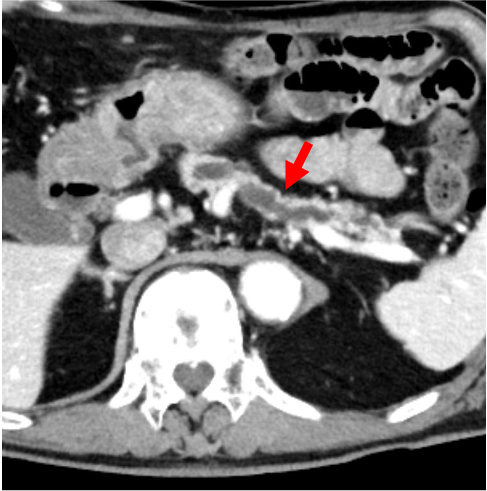

膵癌は、乏血性の境界不明瞭な腫瘤で、造影後期相で漸増性濃染を示すとともに、上流側主膵管の拡張を示すが、本症例はこの典型像に合致していた。主膵管拡張を来す乏血性の腫瘤の鑑別としては、groove pancreatitisなどの良性病変もあるが、膵頭部癌との鑑別は非常に困難とされており1)、疑わしい症例は早期に内視鏡下生検などの精査を依頼するのが望ましい。

本症例では造影CTにて膵頭部に乏血性病変を認めた。Vater乳頭部にも近接していたため、胆膵内視鏡(ERCP)にて検体採取が可能と判断し、病理学的精査を推奨した。消化器内科にて超音波内視鏡下生検(EUS-FNA)を施行、浸潤性膵管癌(invasive ductal adenocarcinoma)の診断が確定した。近傍のSMAへの浸潤はなく、遠隔転移もなかったことから切除可能であり、約7週間後に消化器外科にて膵頭十二指腸切除術を実施、その後順調な経過をたどっている。